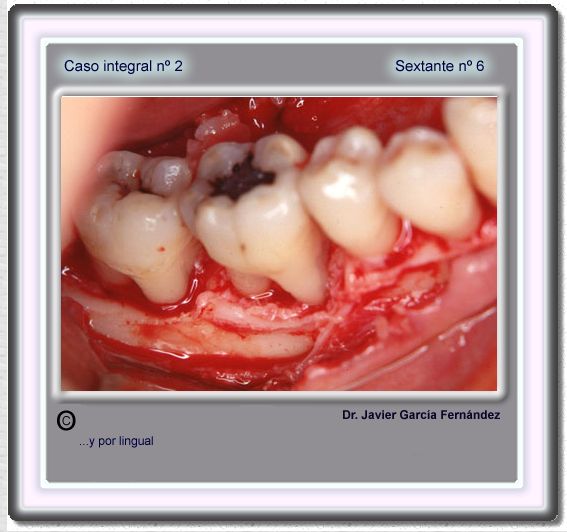

image 77